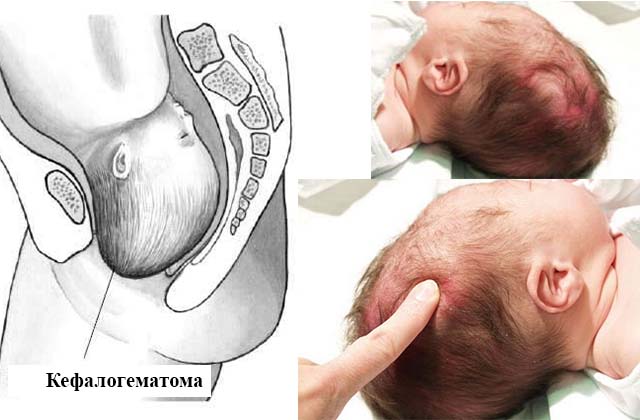

Кефалогематома

Диагностируются такие образования при разрыве сосудов и накоплении крови между косточками головы и надкостницей. За пределы костей черепа кефалогематома не распространяется и не вызывает изменения цвета кожи и болезненных ощущений.

- кефалогематома — в результате повреждения сосудов и образование кровяных сгустков между надкостницей и черепом;

Возникновение кефалогематомы

Эта патология возникает у 2 % малышей и у 1,5 % проходит без дальнейших последствий. Кефалогематома в течение 2-3 дней с момента появления может увеличиваться в размерах. Это связано с плохой свертываемостью крови у младенцев, которая со временем проходит. Такой сгусток может содержать от 5 до 150 мл жидкости внутри.

Локализация ее чаще происходит на теменных костях. Впереди и сзади эта гематома очень редко встречается. Образование обычно захватывает место только над одной частью кости черепа.

Кефалогематома

Кефалогематома у новорожденного формируется после выхода на свет или же спустя 2-3 суток. В большинстве случаев гематома проходит самостоятельно и не оказывает негативное воздействие на здоровье новорожденнного. Ее размер увеличивается в первый и второй день на фоне дефицита свертывающей функции крови.

Место локализации кефалогематомы у младенца – между надкостницей и костью черепа. Таковая не распространяется за границы пораженной кости и оснащена четкими краями. Размер в пределах от 3 до 7 см.

При ощупывании головы обнаруживают новообразование с упругой и мягкой консистенцией, валикообразное уплотнение по периферии. Кровоизлияния размером более 8 см требуют вмешательства хирурга, ведь самостоятельное рассасывание в данном случается достаточно редко.

Что такое гематома или кефалогематома

Кефалогематома – это особый вид кровоподтека на голове ребенка. Представляет собой кровавую припухлость в области между надкостницей и плоскими костями черепа. Если выражаться обиходным языком, то это синяк, возникший из-за повреждения мягких тканей.

Внешне гематому сложно принять за синяк. Цвет кожного покрова на месте травмы не меняется, слегка становятся заметны точечные кровоизлияния. Визуально кефалогематома выглядит, как шарик, в котором при пальпации перекатывается жидкость.

- Кефалогематома. Скопление крови наблюдается между черепом и надкостницей. Встречается нечасто, у 2% малышей.

После родов на голове у новорожденного чаще всего возникает кефалогематома. Для нее характерно накопление жидкости между черепной костью и окружающими тканями. Если шишка небольшая, она самостоятельно рассасывается через 1-2 недели. Обычно серьезного врачебного вмешательства не требуется. Ребенок хорошо себя чувствует и полноценно развивается.

1) Кефалогематомы: имеют наиболее благоприятный прогноз. Представляют собой кровоподтек, находящийся между надкостницей и черепом. Объем кефалогематомы увеличивается на протяжении нескольких дней и может достигать 150 миллилитров. Кровь кефалогематомы остается жидкой, затем медленно начинает сворачиваться. Если гематома незначительная, то она не требует лечения.

Примерно через неделю после родов кефалогематома начинает рассасываться, а ко второму месяцу она и вовсе исчезает. Крупная гематома рассасывается медленно. Кроме того, кровь, содержащаяся в ней, может проникнуть в окружающие мягкие ткани. По этой причине в кровоток ребенка попадет некоторое количество билирубина, что может привести к развитию желтухи. Также в области кровоизлияния надкостница головы уплотняется, а сама кефалогематома окостеневает, из-за чего на головке у ребенка возникает шишка. Крупная кефалогематома требует лечения — с помощью двух игл врач откачивает кровь и накладывает на место расположения гематомы стерильную повязку.